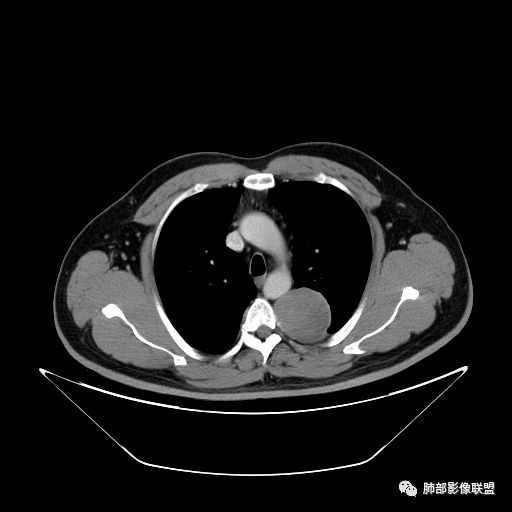

红日东升:左侧胸椎旁肿块,边缘清晰光整,冠状位见D字征,未见支气管进入,肺组织受压表现,定位肺外。轻度强化,密度稍不均匀,临近肋骨变细,未见肺动脉供血,考虑良性肿瘤,神经源性可能。右肺下叶病灶,轻度强化,血管显影,边缘平直、凹陷,考虑炎性病变。

左肺下叶脊柱旁病灶,可见胸膜尾征,均匀强化,临近椎间孔未见扩大,考虑孤立纤维瘤,鉴别诊断神经源性肿瘤,右肺下叶病灶边缘平直,明显均匀强化,边缘清楚,考虑机化性肺炎。

张帅:患者中年男性,咳嗽 咳痰3月,痰为白色粘痰,左上肺病灶,边缘光滑,周围未见毛刺 分叶,肺组织受挤压,与胸膜关系密切,部分层面与胸膜脂肪间隙消失,有胸膜尾征,病灶定位于胸膜,病灶增强可见强化,边缘可见增强血管,内可见低密度区,考虑 孤立胸膜纤维瘤?神经鞘瘤?右肺下叶外基底段病灶,病灶与胸膜有牵拉,病灶边缘光滑,平直 u型征,未见明显毛刺,增强病灶内可见增强血管影,边缘低密度,考虑病灶内存在痰栓。右下肺病灶考虑良性炎症性病灶,ABPA?

张立:左侧胸椎旁肿块,边缘清晰光整,冠状位见D字征,未见支气管进入,肺组织受压表现,定位肺外。轻度强化,密度稍不均匀,,未见肺动脉供血,神经源性肿瘤,节细胞神经瘤可能。右肺下叶病灶,轻度强化,血管显影,边缘平直、凹陷,TB可能。

可芸:定位:肺外病变,胸椎旁肿块,边缘清晰光整,可见胸膜尾征无支气管进入,肺组织受压。轻度强化,密度稍不均匀,未见肺动脉供血,考虑良性肿瘤,神经源性,孤立性纤维瘤?右肺下叶病灶,轻度强化,血管显影,边缘平直、凹陷,炎性病变。

王秀仙:左侧后纵膈占位,位于胸膜下,胸膜被顶起,有胸膜尾征,密度均匀,轻度强化,内可见斑点钙化。周围肺组织结构推移。右肺下叶可见片状影,沿支气管走行,边缘平直收缩,强化明显,胸膜有牵拉。二元论,考虑1左侧后纵膈神经鞘瘤。鉴别SFT.2右肺下叶炎性肉芽肿。

薏米:左下近脊柱旁可见一结节状密度增高影,肺外,边界清,边缘规整,无分叶,无毛刺,无棘突,宽基底与胸膜相连,不均匀轻度强化,考虑为良性病变,神经源性可能性大,为神经鞘瘤,鉴别孤立性神经纤维瘤,神经节瘤,右肺片装密度增高影,考虑为炎症可能性大

崇军:左侧胸椎旁肿块,边缘清晰光整,有胸膜尾征,冠状位为D字征,定位肺外。轻度强化,密度稍不均匀,似乎看到肋间动脉供血,未见肺动脉供血,考虑良性肿瘤,神经源性可能。右肺下叶病灶,轻度强化,血管显影,边缘平直、凹陷,层面太少,暂时考虑炎性病变。

长沟流月去无声:中年男性,慢咳起病,左后纵隔可见一大占位,D字征,胸膜掀起,有胸膜尾征,附近肺组织受挤压,血管纹理纠集,瘤肺界面清晰,较均匀轻-中度强化,瘤肺表面可见线样不张之强化影,供血血管来源不易确定,冠状位似乎见一纵隔血管出入,综合考虑神经源性肿瘤:神经纤维瘤,神经鞘瘤?右下外斑片密度影,估计炎性,但本次手术应该未处理。

张秀兰:定位:肺外来源没问题表现,紧贴胸壁,胸膜尾征,点状钙化,密度均 匀,轻度强化考虑:神经源性肿瘤,鞘瘤首选,节细胞瘤待排鉴别:1单发胸膜间皮瘤,间皮瘤也有强化,程度比这个略甚,少见2孤立性纤维瘤,血供丰富,小的瘤体也有比较明显的强化,瘤体越大滋养血管越丰富,强化越甚。

ZK金:定位:左肺下叶后综合脊柱旁肺外肿块,胸膜尾征,D字征,瘤肺交界面清晰,肺组织受压。影像表现:边界清晰,密度均匀,上下经线略横经。首先考虑神经源性肿瘤,神经节细胞瘤首选,鞘瘤和孤立性纤维瘤鉴别诊断。右肺下叶考虑炎症。

1.左上胸内脊柱旁半圆形肿块,质地坚实,密度比较均匀。

2.病灶周边见胸膜掀起,应当考虑胸壁或是纵隔来源,肺内病变不会如此。

3.降主动脉这一相对固定结构向前方推移,提示病灶相对坚实且有牢固附着点,不支持来自柔软的肺组织。

4.可疑肋间动脉病供血,提示肿块来自后纵隔的可能性。

5.相邻椎间孔未见扩大,也未见块影延入椎管,易起自于神经根的鞘瘤似乎找不到相关支持点。

7.静脉期轻度强化,注意不是环形强化,亦未显示明确的“AB区”,神经鞘瘤与副节瘤亦未找到支持点。

综上,病灶定位胸壁或后纵隔,就发病率而言,神经源性可能性较大。